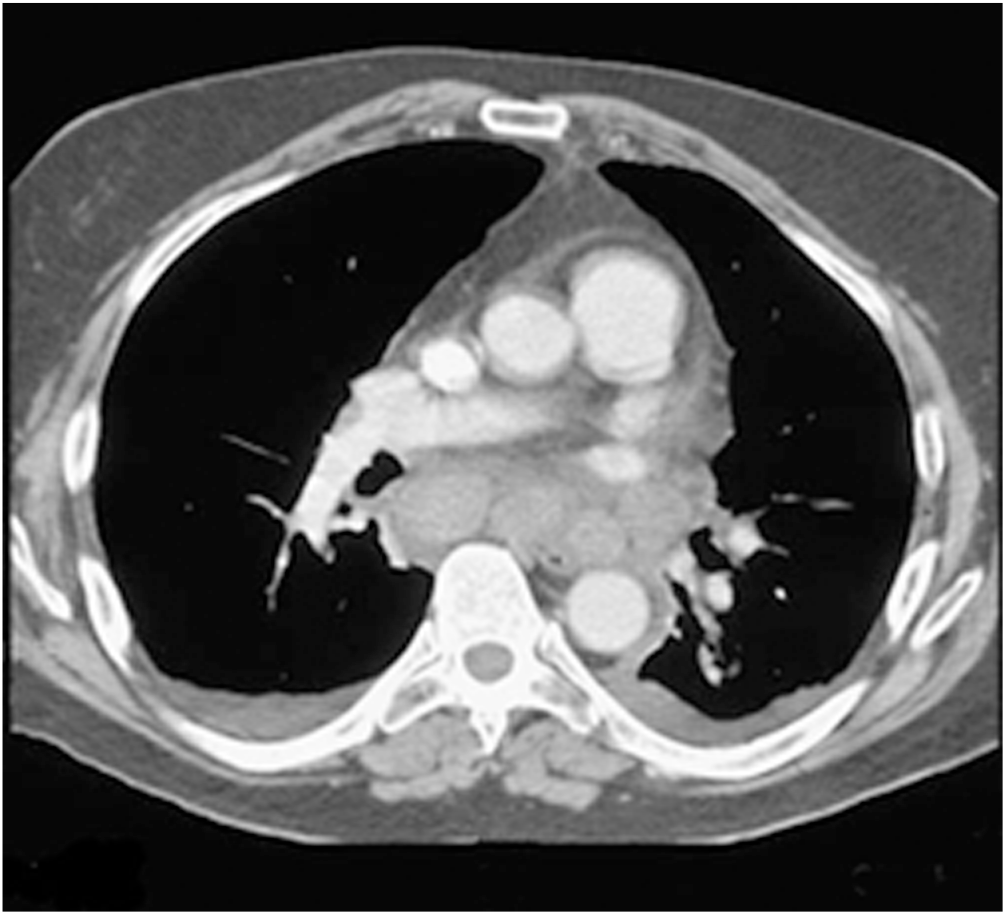

Coma, Cognitive Impairment, and Seizures

- When treating an unresponsive patient, targeted therapy is advised instead of routine use of the “coma cocktail” (empirical treatment with dextrose, naloxone, thiamine, and sometimes flumazenil).

- Avoidance of hypotension and maintenance of normoglycemia and normothermia are critical to the management of intracranial hypertension.

- Differing levels of awareness were noted among patients found to be in a minimally conscious state (MCS); subsequently, this condition was further subdivided into two categories, MCS plus (MCS+) and MCS minus (MCS-), based on the ability to follow commands versus just visual pursuit. Permanent vegetative state is no longer used.